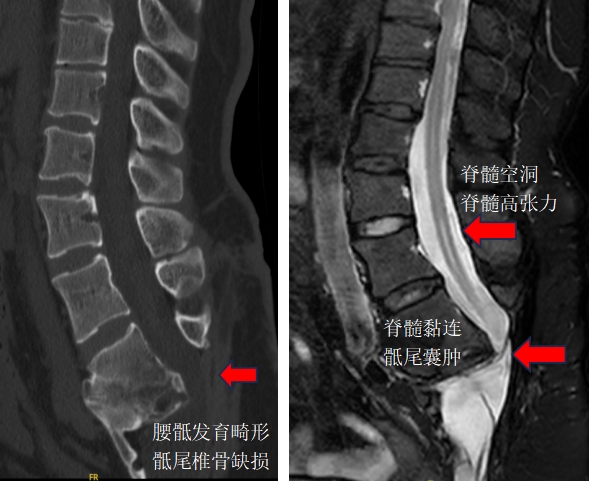

术前腰椎CT和MRI矢状位片

孙振兴及团队考虑到再次松解脊髓和神经黏连,虽然可以直接松解黏连,但面临脑脊液漏、感染和神经损伤的高风险,且脊髓高张力和脊髓空洞难以缓解。因患者的症状与脊髓高张力和空洞有关,而椎体缩短截骨术,可直接降低脊髓高张力,也可避免因松解手术导致的脑脊液漏和神经损伤,但此术会缩短患者身高且手术难度大、手术技术要求高。团队经过综合评估以及跟患者及家属的充分沟通,最终决定选择椎体缩短截骨术为患者进行治疗。